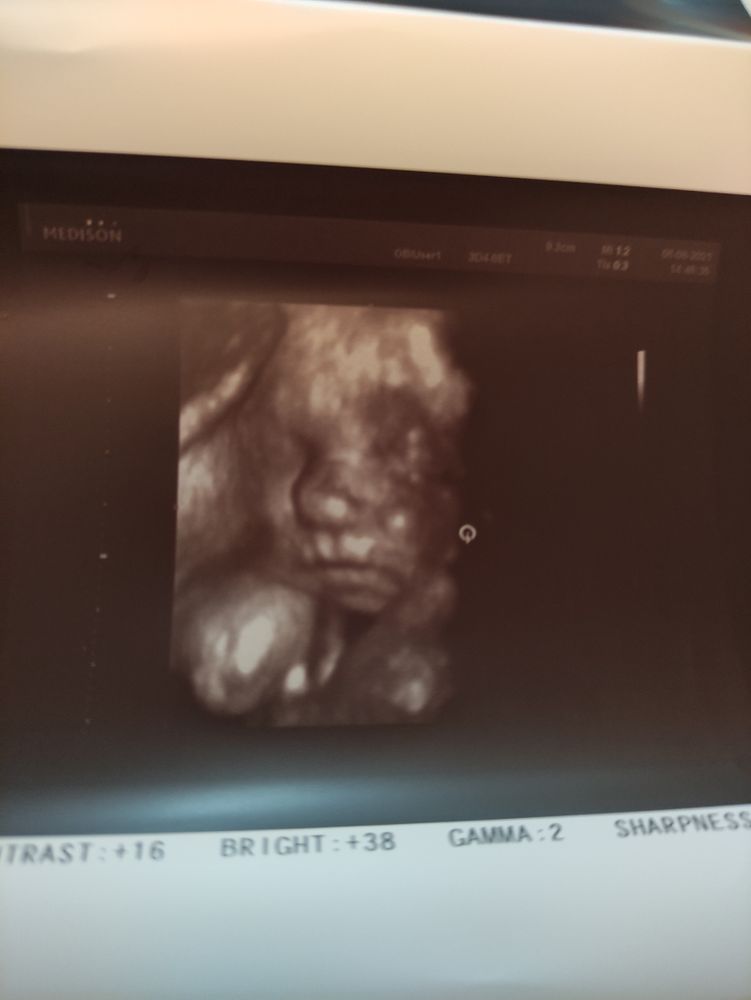

Были на УЗИ увидеть малыша. 26 недель и 2 дня нам сейчас. Вес 907 грам. Все в порядке лишь есть одно обвитие пуповинкой. Это очень страшно?? У кого малыш был тоже так же обвит? Или он может ещё скинуть её? Мне врач сказала ничего страшного нету тут.